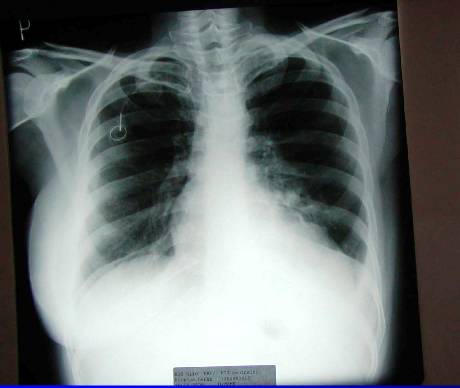

Diferenciální diagnostika

Recidiva Ca mammae

(generalizace do plic)

nebo

Duplicita Ca plic

1.Generalizace (pac.L.U. . ––RTG, CT)

Generalizace (pac.L.U. . ––RTG, CT)